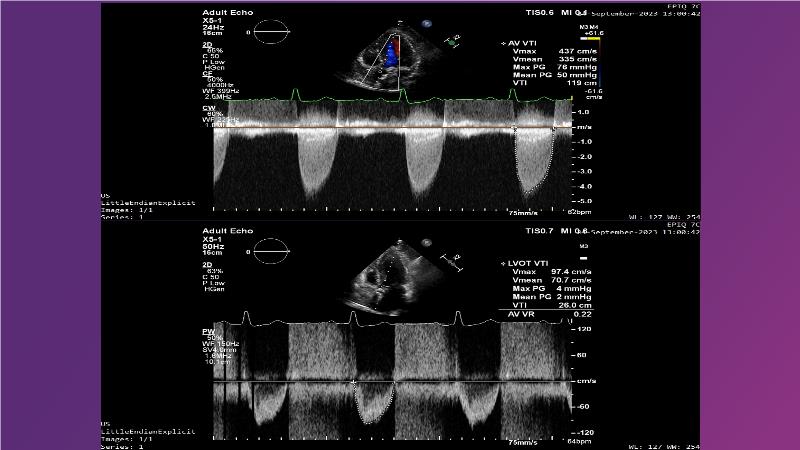

Gain expertise in selecting the appropriate TAVI device for achieving stable deployment in a 90-degree horizontal aorta. Discover techniques for ensuring smooth deliverability, particularly when navigating through tight and tortuous anatomies. Additionally, learn strategies to prepare for future coronary access, irrespective of the height of the left or right coronaries.

• To learn how to select your TAVI device in order to achieve stable deployment in 90 degrees horizontal aorta